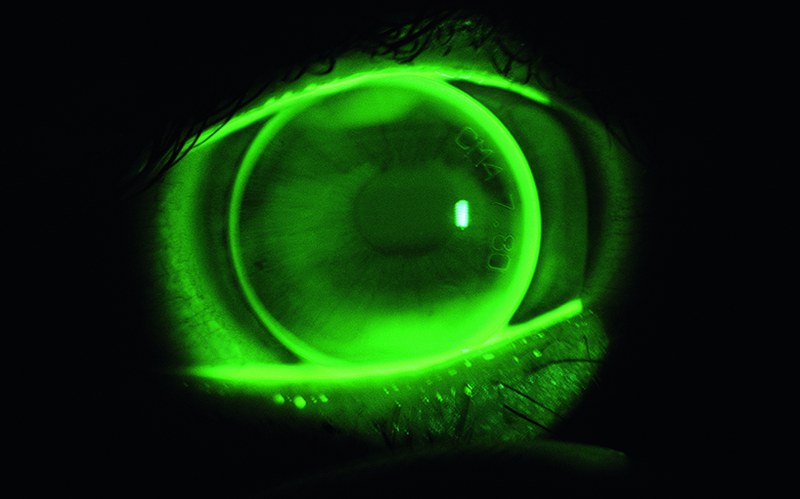

Développement d’une lentille de contact spéciale qui contient un capteur de pression pour la détermination de la pression oculaire.

Le glaucome est la principale cause de cécité. Cette pathologie oculaire est fréquemment liée à une pression intraoculaire accrue. La pression intraoculaire varie fortement au fil du temps, notamment chez les patients atteints de glaucome, et une mesure continue est très importante pour le diagnostic.

L’Institut d’optométrie a pour mission de définir la conception des lentilles, principalement dans la perspective de la compatibilité physiologique et des capacités de mesure physiques.